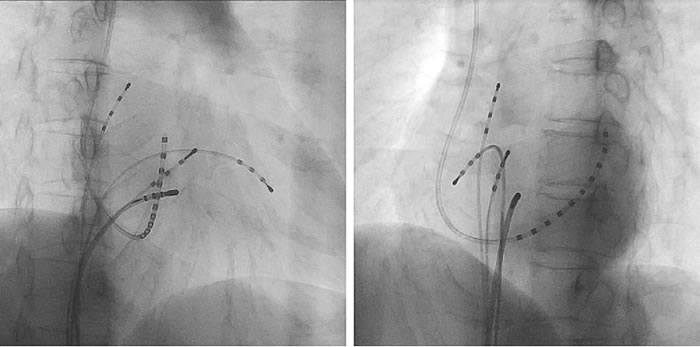

カテーテルは原則右足の付け根の股静脈と、必要に応じて右頸部の静脈を局所麻酔してからカテーテルの水先案内人としてのカテーテルシースを入れます。心臓内にカテーテルを留置してからEPS検査を始めます。実際にカテーテルを留置した時にX線カテーテル装置で透視を行った時の画像を提示します。

EPS用カテーテルの留置画像(左図:右前斜位より見る 右図:左前斜位より見る)